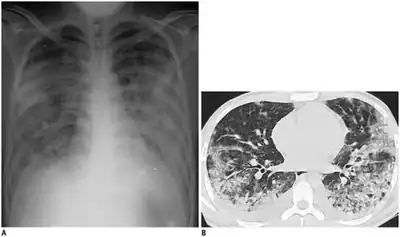

a,b)Adenovirus pneumonia chest X-ray and CT-scan

Diagnosis is from symptoms and history. Tests are only necessary in very serious cases. Tests include blood tests, eyes, nose or throat swabs, stool sample tests, and chest x-rays.[77] In the laboratory, adenovirus can be identified with antigen detection, polymerase chain reaction (PCR), virus isolation and serology. Even if adenovirus is found to be present, it may not be the cause of any symptoms. Some immunocompromised individuals can shed the virus for weeks and show no symptoms.[78]